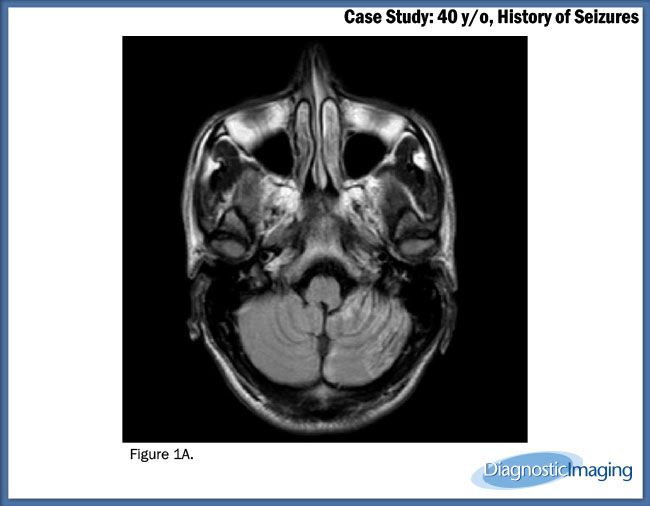

Case History: 40-year-old patient presented with history of seizures.

Case History: A 40-year-old patient presented with history of seizures.